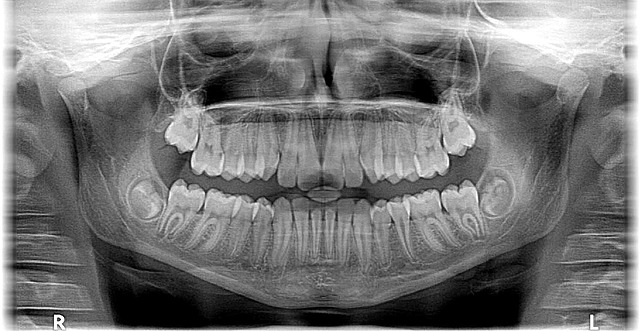

One notable aspect of McAllen’s dental scene is the rise of modern orthodontic clinics that prioritize accessibility and affordability without compromising on results. These practices employ state-of-the-art equipment and utilize evidence-based methods to deliver top-notch care. For instance, clear aligner therapy, an increasingly popular alternative to traditional braces, is now widely available, offering patients a discreet and comfortable treatment option. By leveraging technology and streamlining processes, these orthodontist McAllen clinics are able to offer competitive pricing while maintaining high standards of professionalism.

For example, traditional metal braces often carry a significant price tag, but our office has successfully implemented clear aligner systems like Invisalign® that offer just as effective results—and are virtually invisible. We also provide flexible payment options to make treatment more accessible, allowing families to spread out payments over time. To learn more and get answers at your fingertips – call 956-686-5000 now or visit us at 1632 N. 10th Street, McAllen, TX 78501. You can also reach us by sending an electronic communication to [email protected] for personalized guidance.